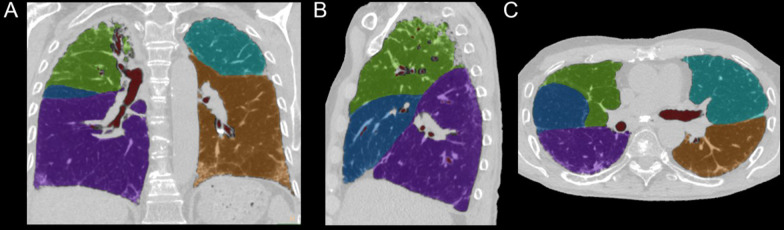

CT images were obtained by full inspiratory HRCT for 2D and 3D volumetric measurements. A radiologist specialized in lung imaging (SSM with 8 years of experience in thoracic imaging) performed a 2D analysis using previously reported parameters, i.e. the transverse tracheal diameter at 1 cm above the carina, the anteroposterior diameter of the thoracic cage (APDT), and the transthoracic transverse diameter of the thoracic cage (TDT) at the level of the fifth dorsal vertebra body scan [18]. A 3D volumetric analysis of the lobar and lung volumes was performed to segment both lung lobes using an appropriate semi-automatic software (COPD, IntelliSpace Portal, Philips) [23]. This software allowed exclusion of the main pulmonary vessels and adjustments to fissure location and lung borders (Fig. 3). Lung volume changes were calculated by subtracting the last measurement from the first measurement. Positive values represented increased lung volume while negative values reflected decrease in lung volume and disease progression in the corresponding lobe. Annual change was then estimated by multiplying the absolute change by 365 and dividing by the time in days between HRCTs. Results were presented in ml/year.

Fig. 3.

Measurement of lobar lung volume using COPD software (IntelliSpace Portal; Philips Healthcare) of chest HR computed tomography (DECT) images (A: coronal, B: Sagittal, C: axial). A specific color has been attributed for each lobe, and lobar volume was derived